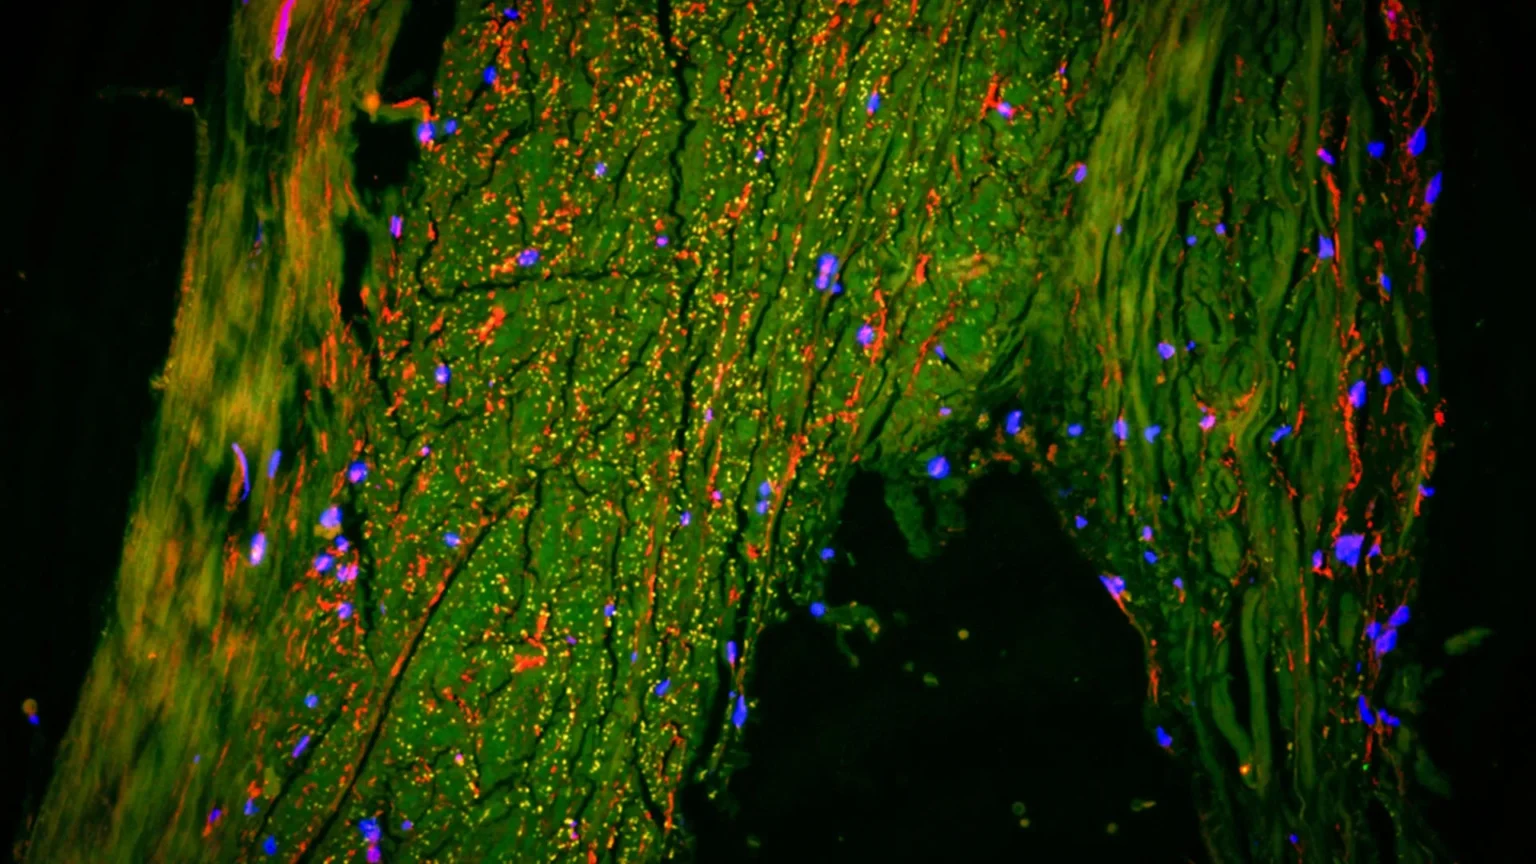

To verify their findings, the researchers also examined human brain tissue using ultra-high resolution images. Working with scientists at Cornell University, they used a method that allows them to observe multiple cell types simultaneously.

This detailed analysis showed that the area surrounding the MMA contained cells normally found in lymphatic vessels. These are the same type of structures that are responsible for removing waste products throughout the body.